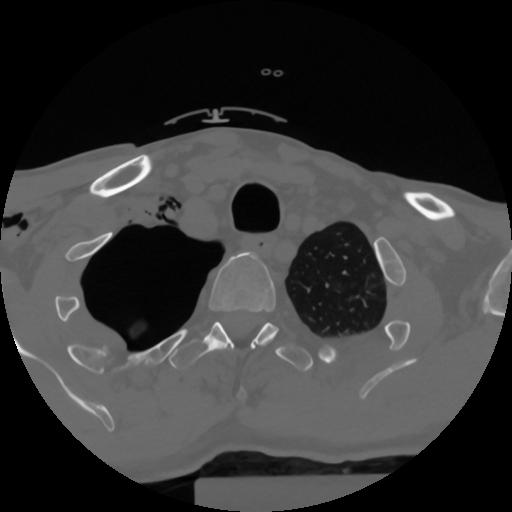

12 P.BLANDAS,,Vol,0.5,P.BLANDAS,,